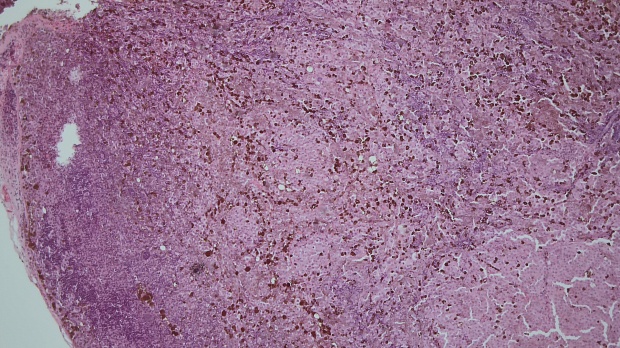

В Январе 2024: выполнено иссечение правого пахового л/узла с последующей гистологией.

Гистологическое заключение : Метастаз пигментной меланомы в лимфатическои узле.